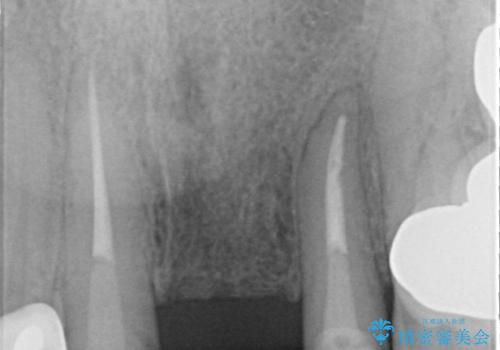

歯肉縁下カリエスも認められるため、挺出を行いセラミックブリッジを審美的に新製します。

挺出について

虫歯が深くなった場合、挺出や歯周外科を行い歯周組織の状態を改善することでより安定した状態で予知性の高いセラミックブリッジを製作することが可能となります。